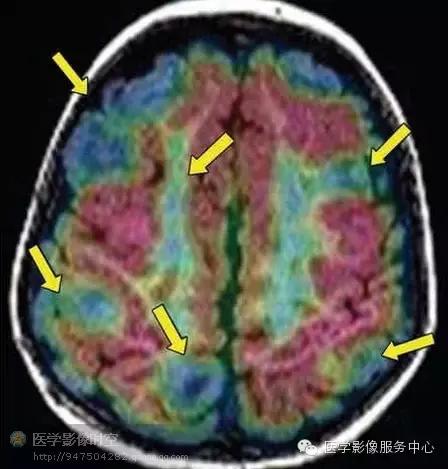

扩散张量成像是一种利用水分子扩散各向异性来反映微观结构的成像技术。白质的水分子在神经纤维束平行方向扩散程度大,而在其它方向上扩散程度小,根据该特点可以显示神经纤维束信息。在扩散张量图像上,每一个体素给予不同的颜色,反映水分子在横断、矢状和冠状方向上主要的弥散方向。常规情况下,蓝色代表着上下扩散方向,绿色代表的是前后扩散方向,红色代表的是左右扩散方向。另外,扩散张量图像可以显示为三维图像,一般称为纤维示踪图。也可以根据扩散张量成像中各向异性的差异来鉴别正常的组织和病变组织。

MR-PET融合图像通过软件配合MR图像和PET图像来实现。两组数据独立采集,但是病人摆位上需要类似,以便于图像配准。该技术可以直接关联MR发现的结构上的异常与PET发现的代谢异常。在发作间期,代谢异常的区域表现为低代谢,而在发作期,病变表现为高代谢。很多在常规磁共振上容易忽略的轻微异常,在融合图像上表现更加突出。

图2 a b 3岁男孩Ⅱ型局部皮质发育不良。

图2a横断T2WI显示局部灰白质交界区模糊(箭头所示)及右侧额下回异常T2高信号影(箭)。

图2b横断MR-PET融合图像显示局部低代谢(箭)。病理学检查显示ⅡB型局部皮质发育不良。

目前的影像学检查方法,包括磁共振成像,磁源成像,或者PET尚不能可靠的鉴别轻度皮质发育不良,局部皮质发育不良Ⅰ型和Ⅱ型(图1-6)。但是,如果发现皮层下T2高信号,尤其是延伸到侧脑室,常常是ⅡB型(图2)。目前认为T2高信号是髓鞘化程度低造成的,而非气球样细胞所致。其它的局部皮质发育不良的典型磁共振成像表现包括局部皮质增厚,灰白质界限模糊,灰质高信号(图6)。

局部皮质发育不良的影像学表现可以非常轻微,仅靠磁共振成像容易漏诊。MR-PET融合图像和磁源成像有助于定位磁共振成像所见的轻微结构异常和异常信号。发作间期PET检查可以显示局部皮质发育不良累及皮层区显示为低代谢(图1,3-5)。发作间期磁源成像显示局部皮质发育不良的脑皮层癫痫样放电灶(图3a,4b)